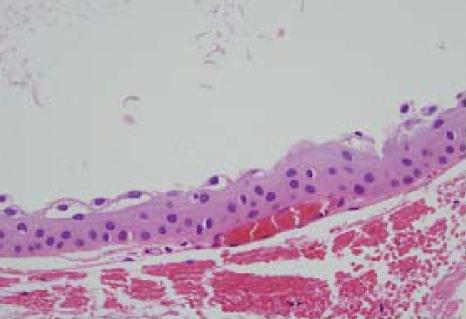

On histopathological examination, the conjunctival cysts consisted of nonkeratinizing stratified epithelial cells filled with PAS-positive mucous substance. Inflammatory cells were not found in the vicinity.